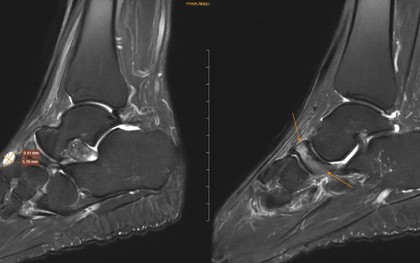

Đi khám vì đau cổ chân không rõ nguyên nhân, nữ giáo viên phát hiện ra xương bên trong đang bị tự hủy.